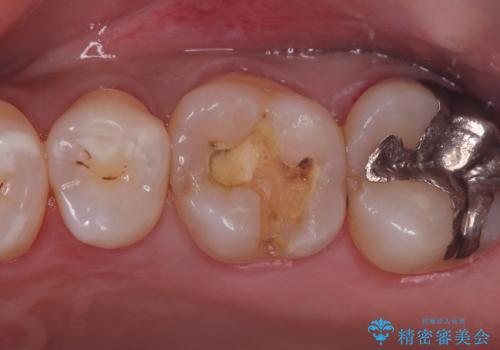

保険適用のメタルインレーと歯質の境目にう窩ができており、補綴物のやり替えとなりなした。

メタルインレーを除去したところう窩が深く、遠心の健歯質が歯肉縁下深くに位置したためディスタルウェッジ術を行い骨と歯肉の高さを下げた上で補綴しています。

元々インレーが入っていましたが、残存歯質量が少なく破折のリスクを説明しジルコニアクラウンでのやり替えとなりました。